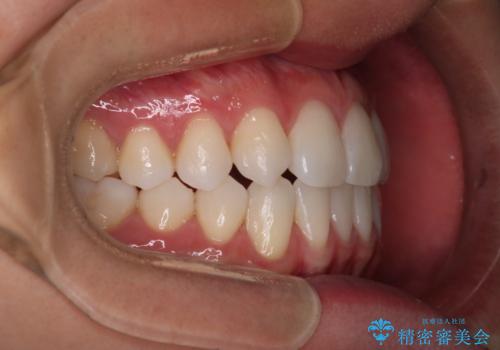

【インビザライン】歯の本数少ないのにがたつきがある セラミックインレー

右上2番が欠損しているため、見た目と噛み合わせの両方のバランスを整えるために経過を追いながら必要な部位にゴム掛けをしました。

最終的に、見た目も噛み合わせも患者様に満足いただけました。

また矯正後、患者様の希望で

メタルインレーをセラミックインレーにやりかえさせていただき、さらに綺麗に仕上がりました。